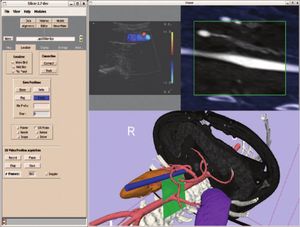

Boolean Combinations of Implicit Functions for Model Clipping in Computer-Assisted Surgical Planning

Publication: PLoS One. 2016 Jan 11;11(1):e0145987. PMID: 26751685 | PDF Authors: Zhan Q, Chen X. Institution: School of Mechanical Engineering, Shanghai Jiao Tong University, Shanghai, China. Background/Purpose: This paper proposes an interactive method of model clipping for computer-assisted surgical planning. The model is separated by a data filter that is defined by the implicit function of the clipping path. Being interactive to surgeons, the clipping path that is composed of the plane widgets can be manually repositioned along the desirable presurgical path, which means that surgeons can produce any accurate shape of the clipped model. The implicit function is acquired through a recursive algorithm based on the Boolean combinations (including Boolean union and Boolean intersection) of a series of plane widgets' implicit functions. The algorithm is evaluated as highly efficient because the best time performance of the algorithm is linear, which applies to most of the cases in the computer-assisted surgical planning. Based on the above stated algorithm, a user-friendly module named SmartModelClip is developed on the basis of Slicer platform and VTK. A number of arbitrary clipping paths have been tested. Experimental results of presurgical planning for three types of Le Fort fractures and for tumor removal demonstrate the high reliability and efficiency of our recursive algorithm and robustness of the module. Funding:

A snapshot of the module SmartModelClip in 3D Slicer. On the left is the operator command view that users can create and manipulate clipping path and thickness plane(i.e., they can create, hide and delete plane widgets). Users can also reverse the directions of the axes of the both clipping path and thickness plane widget. On the right is the scene that users can interact with the clipping path. They can specify the fiducial points that position the clipping path and modify the boundary of the clipping path by dragging the handles to obtain the desirable clipping path. |